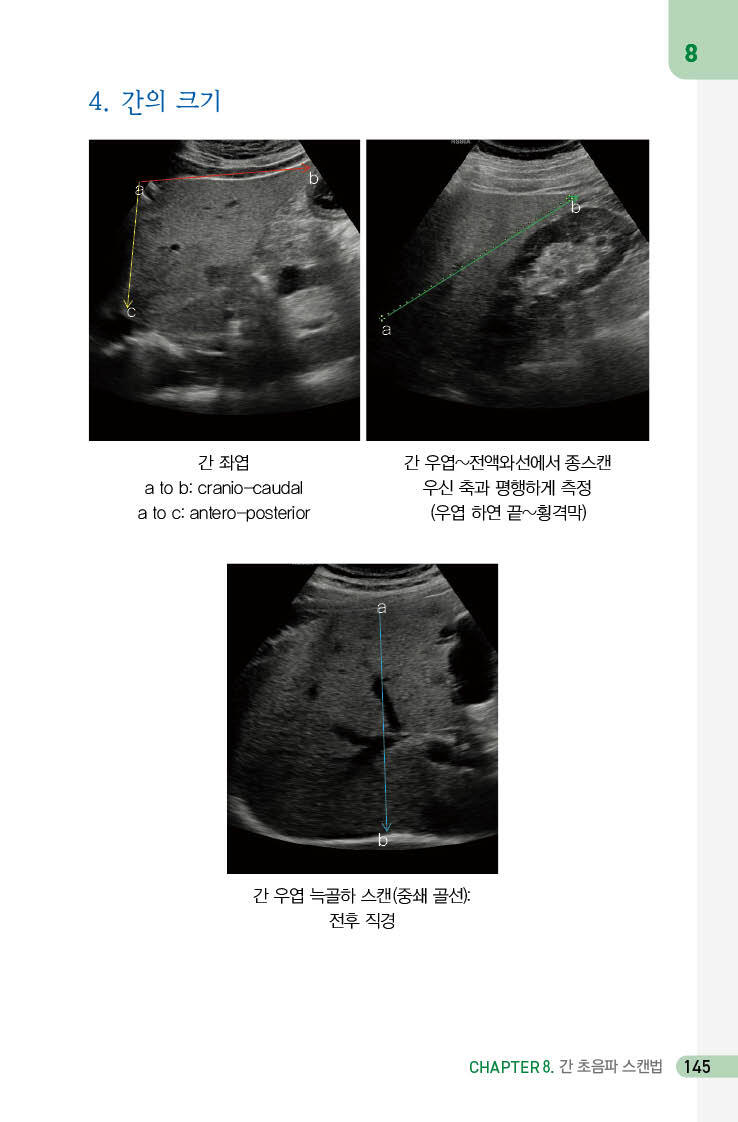

4. 간의 크기 145